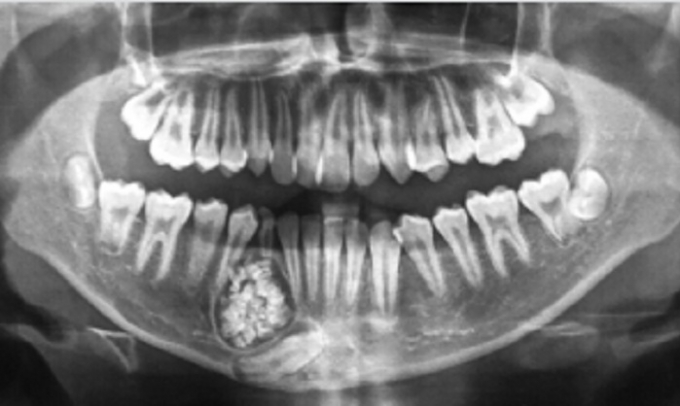

Hình ảnh chụp X- quang khối u răng trong miệng bé trai.

Nguyên nhân do răng hàm dưới của cậu bé mọc lệch và chậm thay răng mới. Tuy nhiên, qua chụp X-quang, các bác sĩ phát hiện có một khối u răng ở xương hàm dưới. Sau khi hội chẩn qua hình ảnh, các bác sĩ của Bệnh viện Răng hàm mặt Trung ương TP.HCM đã ra Bệnh viện Đa khoa tỉnh Khánh Hòa thực hiện mổ cho bệnh nhi.

Sau một tiếng đồng hồ phẫu thuật, các bác sĩ đã lấy ra gần 100 chiếc răng nhỏ li ti có đầy đủ thân răng, tủy răng và chân răng từ khối u của bệnh nhân. Bác sĩ Tuấn cho biết, u răng hay còn gọi là ComplexOdontoma, là một trong những loại u lành tính và rất hiếm gặp ở nước ta. U thường diễn tiến âm thầm, ít gây ra triệu chứng nên khó phát hiện sớm.

U răng rất khó phát hiện, chỉ qua phim chụp Xquang mới có thể nhìn thấy. Chính vì thế, rất nhiều bệnh nhân điều trịsai cách, loại bỏ u không triệt để, nên bệnh tiến triển ngày một nặng, dẫn đến gãy xương hàm, đứt dây thần kinh.